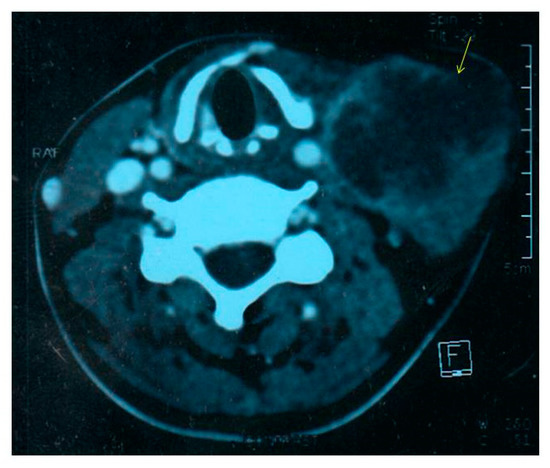

Contrast enhanced computed tomography (CECT) scan of the neck showed the presence of a large, heterogenous enhancing hypodense nodal mass in left cervical region (Figure 1), likely to represent a pyogenic or tuberculous abscess. A fine needle aspirate of the pus sample from the mass showed sheets of neutrophils, degenerated cells, and lymphocytes in a dirty background with no granulomas, necrosis or atypical cells. Mycobacterial smear and culture were negative. Bacterial culture yielded an oxidase-positive gram-negative rod, with an unusual pattern of antibiotic resistance with resistance to colistin, polymyxin B and aminoglycosides. Blood culture was negative. The pus isolate was identified as Burkholderia pseudomallei by its characteristic growth on blood agar and MacConkey’s agar (small, smooth, nonlactose fermenting colonies after overnight incubation, which turned pink with a metallic sheen after 48 h and dry and wrinkled after 96 h of incubation), typical morphology on microscopy (motile, gram negative bacilli with bipolar staining giving a “safety-pin” appearance) and standard biochemical tests (Figure 2) [10,11,12]. The isolate was sensitive to ceftazidime, co-trimoxazole, imipenem, meropenem, doxycycline and amoxicillin—clavulanate [13]. Minimum inhibitory concentration (MIC) of ceftazidime was 4 µg/mL by Etest (bioMérieux, Marcy l’Etoile, France).

Figure 1. Contrast-enhanced CT neck showing left cervical abscess.